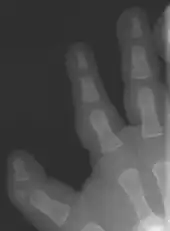

In combination with polydactyly

The triphalangeal thumb has a different appearance than normal thumbs. The appearance can differ widely; the thumb can be a longer thumb, it can be deviated in the radio-ulnar plane (clinodactyly), or thumb strength can be diminished. In the case of a five-fingered hand it has a finger-like appearance, with the position in the plane of the four fingers, thenar muscle deficiency, and additional length. There is often a combination with radial polydactyly.

There are multiple classifications for the triphalangeal thumb. The reason for these different classifications is the heterogeneity in appearance of the TPT. The classification according to Wood [9] describes the shape of the extra phalanx: delta (Fig. 4), rectangular or full phalanx (Table 1). With the classification made by Buck-Gramcko a surgical treatment can be chosen (Table 1). Buck-Gramcko differentiates between six different shapes of the extra phalanx and associated malformations.[10]